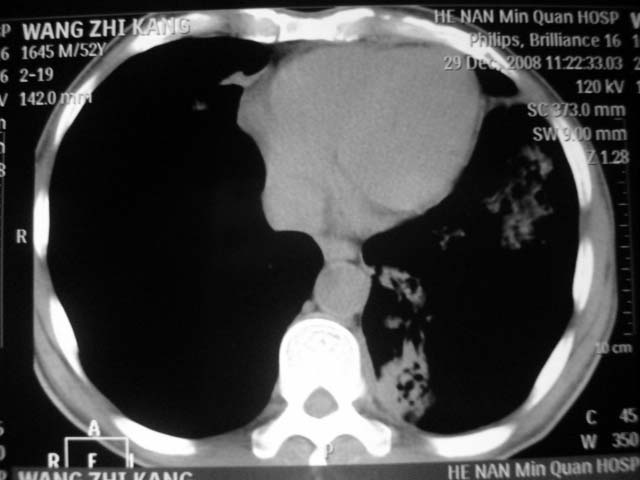

男,52岁,发热2月,糖尿病史。

抗结核治疗irpz方案,血糖未治疗,空腹15.9左右。症状无好转,左胸痛。

复查ct

2、双肺见多发片状及结节状高密度影,大多数病灶中心均见“空泡征”。

3、纵隔内淋巴结肿大。

结果:两肺继发性肺结核并曲霉菌感染。